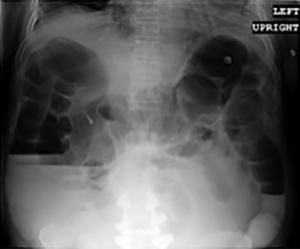

On postoperative day 5, the patient suddenly experienced an acute exacerbation of abdominal pain. An upright abdominal radiograph (Figure 3) demonstrated findings consistent with free air under the diaphragm. A computed tomography scan of the abdomen (Figure 4) demonstrated pneumoperitoneum and dilation of the large and small bowel extending to the splenic flexure. Of note, there was no apparent orthopaedic implant complications or suspicion of mechanical obstruction. He was started on antibiotics and was taken to the operating room by general surgery for an exploratory laparotomy. Intra-operative findings were significant for multiple abdominal adhesions and multiple pinhole sized perforations at the splenic flexure and cecum. Suture repair of all perforations and an adhesiolysis was performed. A nasogastric tube was placed at the end of surgery.